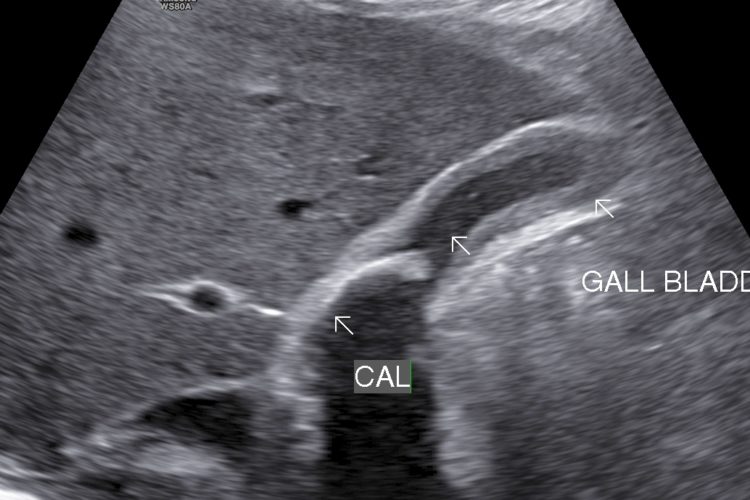

• Cholecystitis: Cholecystitis is Inflammation of gall bladder. Acute calculus cholecystitis results when calculus/calculi get impacted at neck of gall bladder or cystic duct.

• Symptoms: Right upper abdomen, nausea, vomiting & fever(sometimes)

• Finding: Sonography shows thickened oedmatous walls of gall bladder & impacted calculi. Sludge, pericholicystic fluid , localized abscess are additional findings. Sometimes gall bladder is so overdistended that impacted calculi may not be visualized.